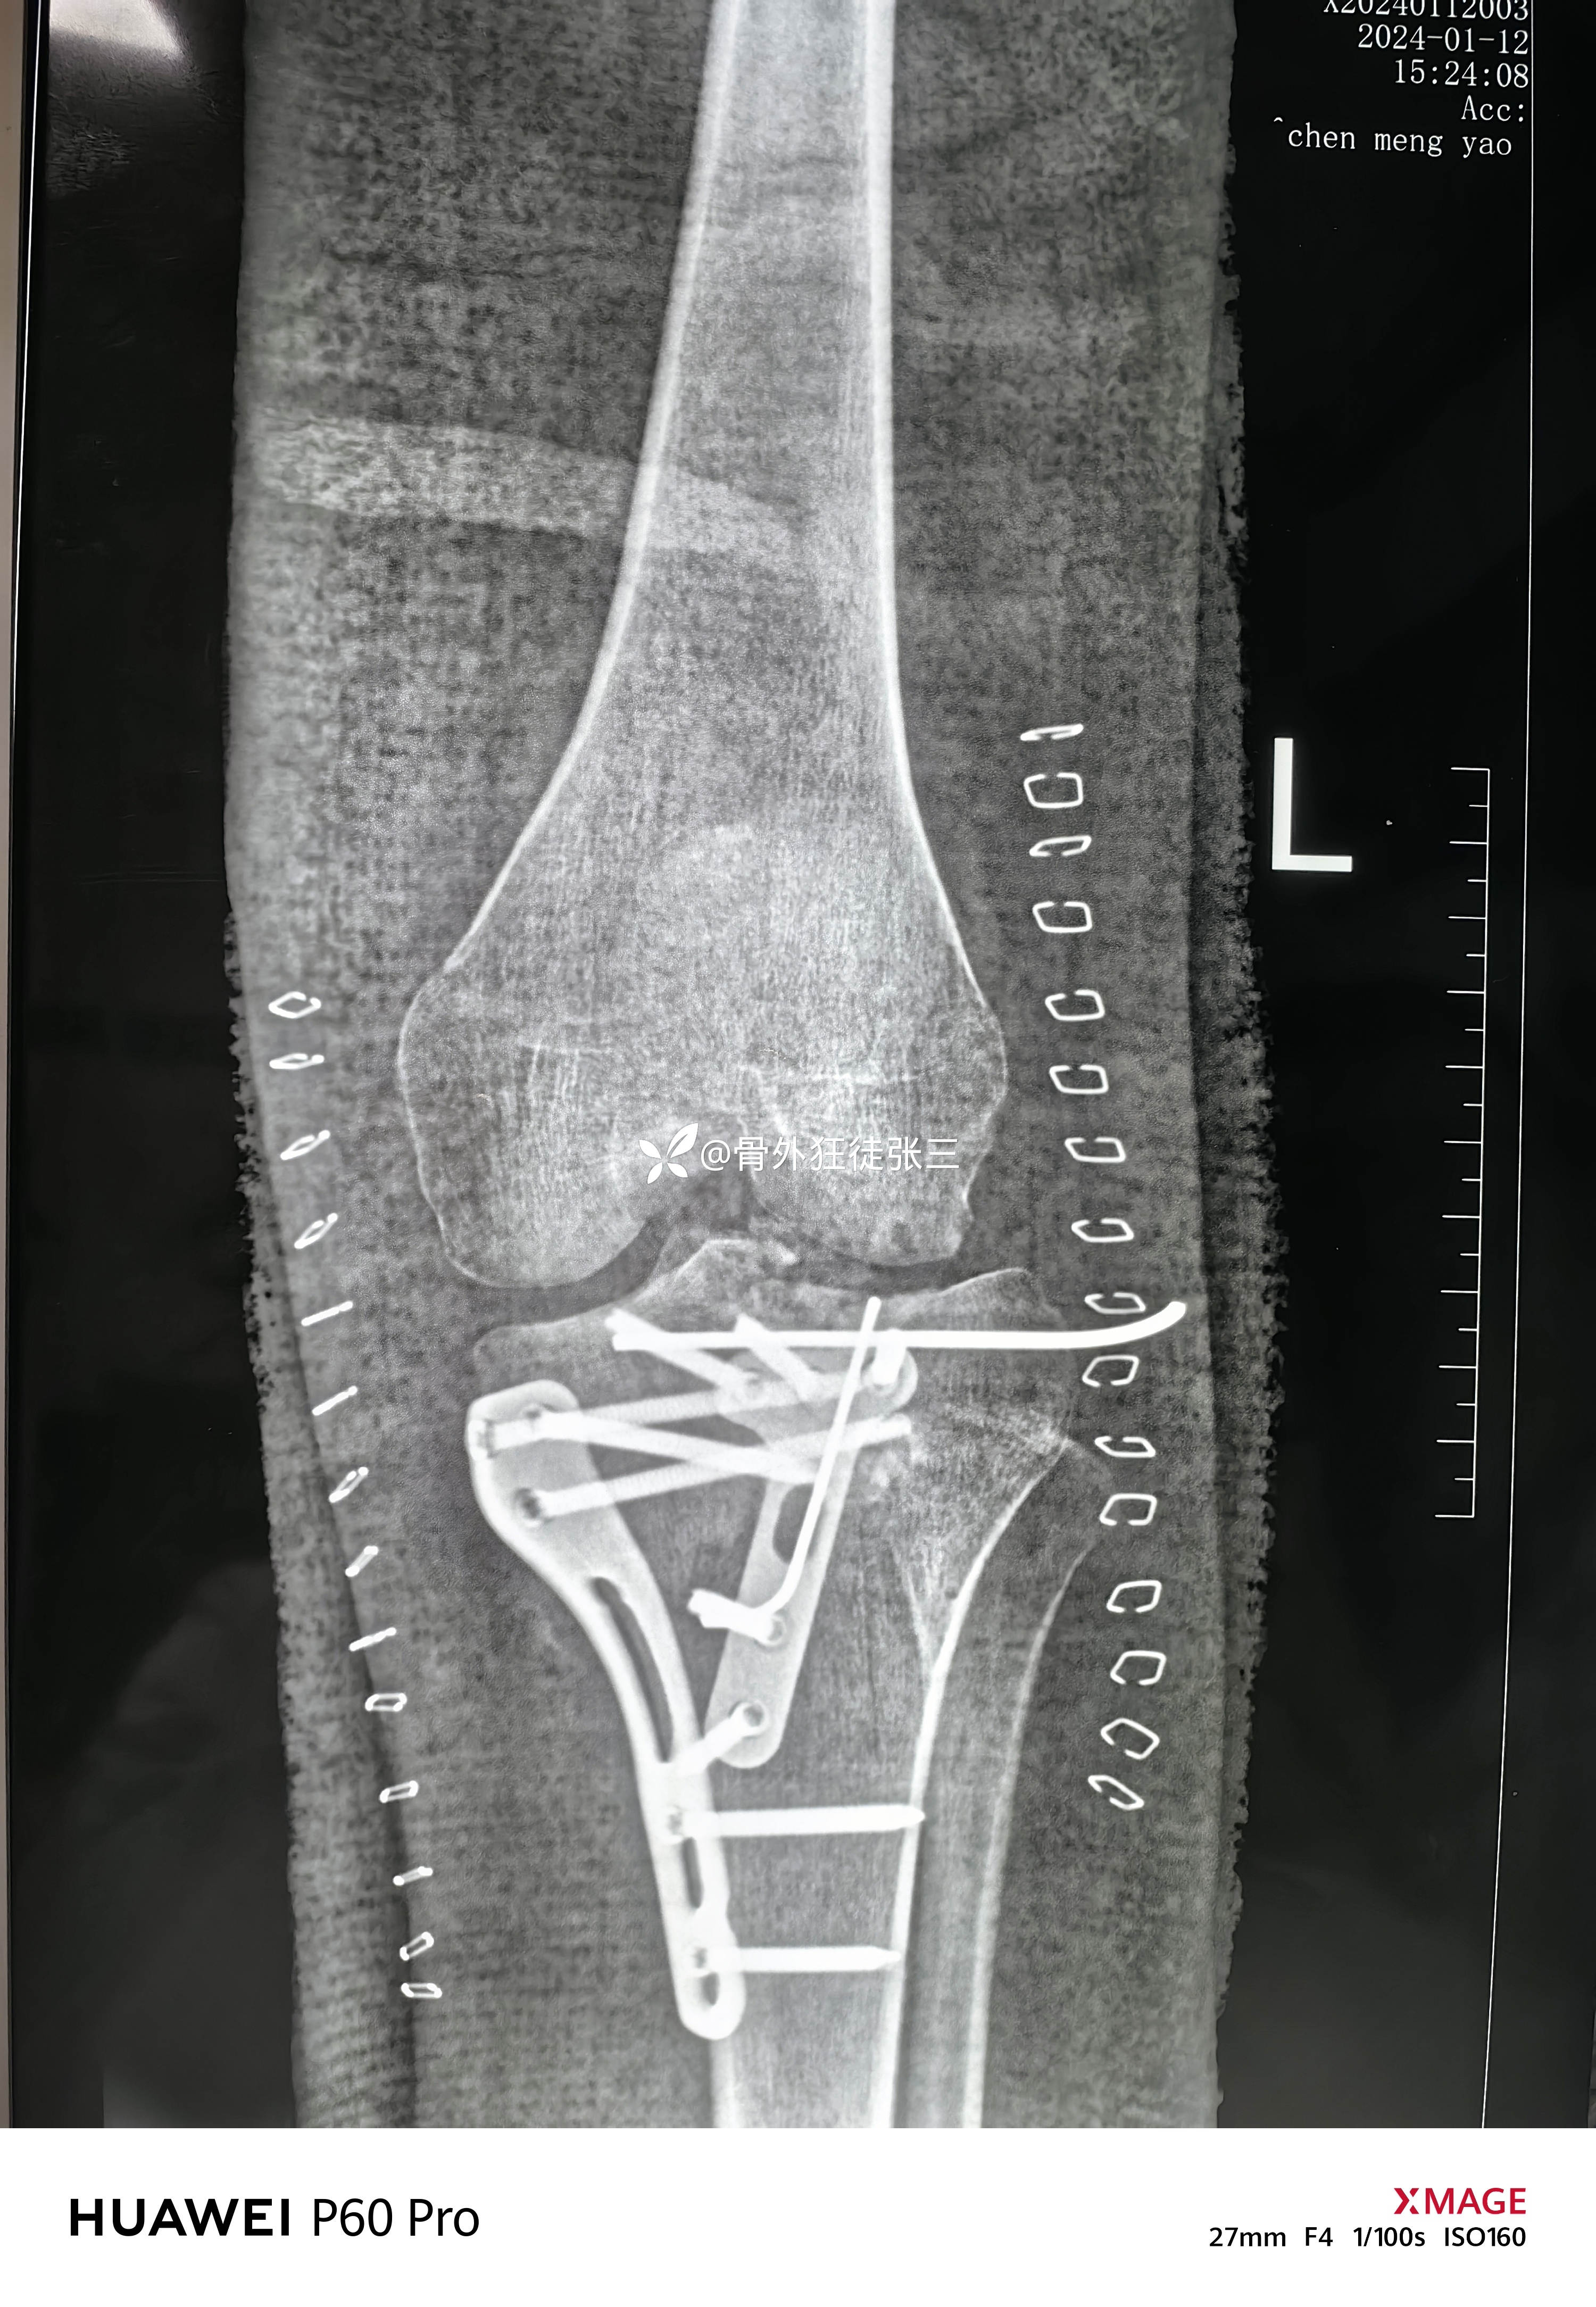

胫骨平台骨折术后,腓总神经损伤,

患者性别:女

患者年龄:19岁

主诉:右胫骨平台骨折术后膝、踝关节活动和感觉障碍3月余。

2023.12.08,在当地医院行胫骨平台骨折手术

2024..01.03,在当地医院行韧带修复术,术后出现感觉和运动障碍

第一次手术后复查

第二次手术后复查